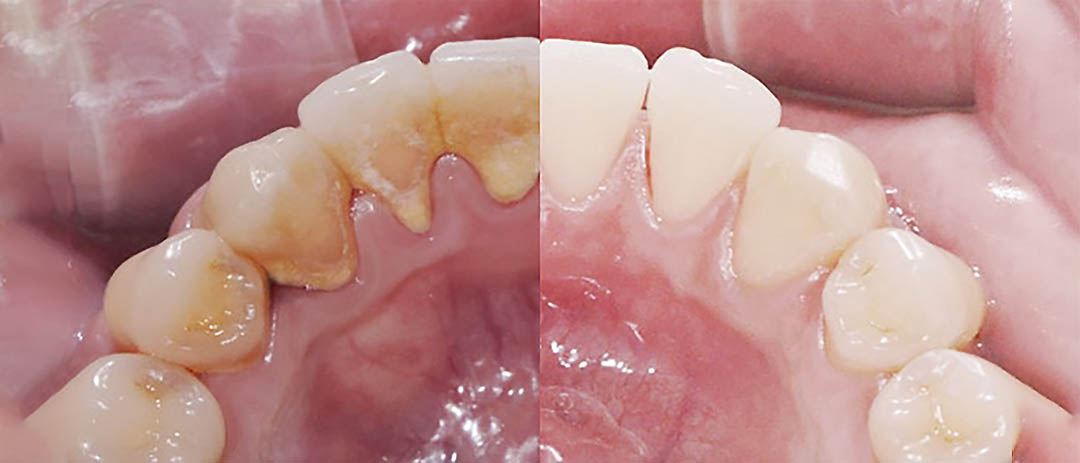

스케일링 하기 전(왼쪽)과 한 후(오른쪽). 양치하기 어려운 안쪽 치아에 치석이 잘 생깁니다.